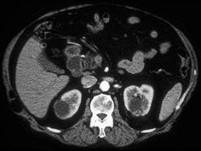

问题 男,54岁,无痛性血尿1个月余,请根据所示图像,选择最可能诊断 ( )

选项 A、右侧肾囊肿合并左侧肾癌 B、多发性肾癌合并肾囊肿 C、多囊肾 D、左侧肾癌并右肾转移 E、多发性肾囊肿

答案 B